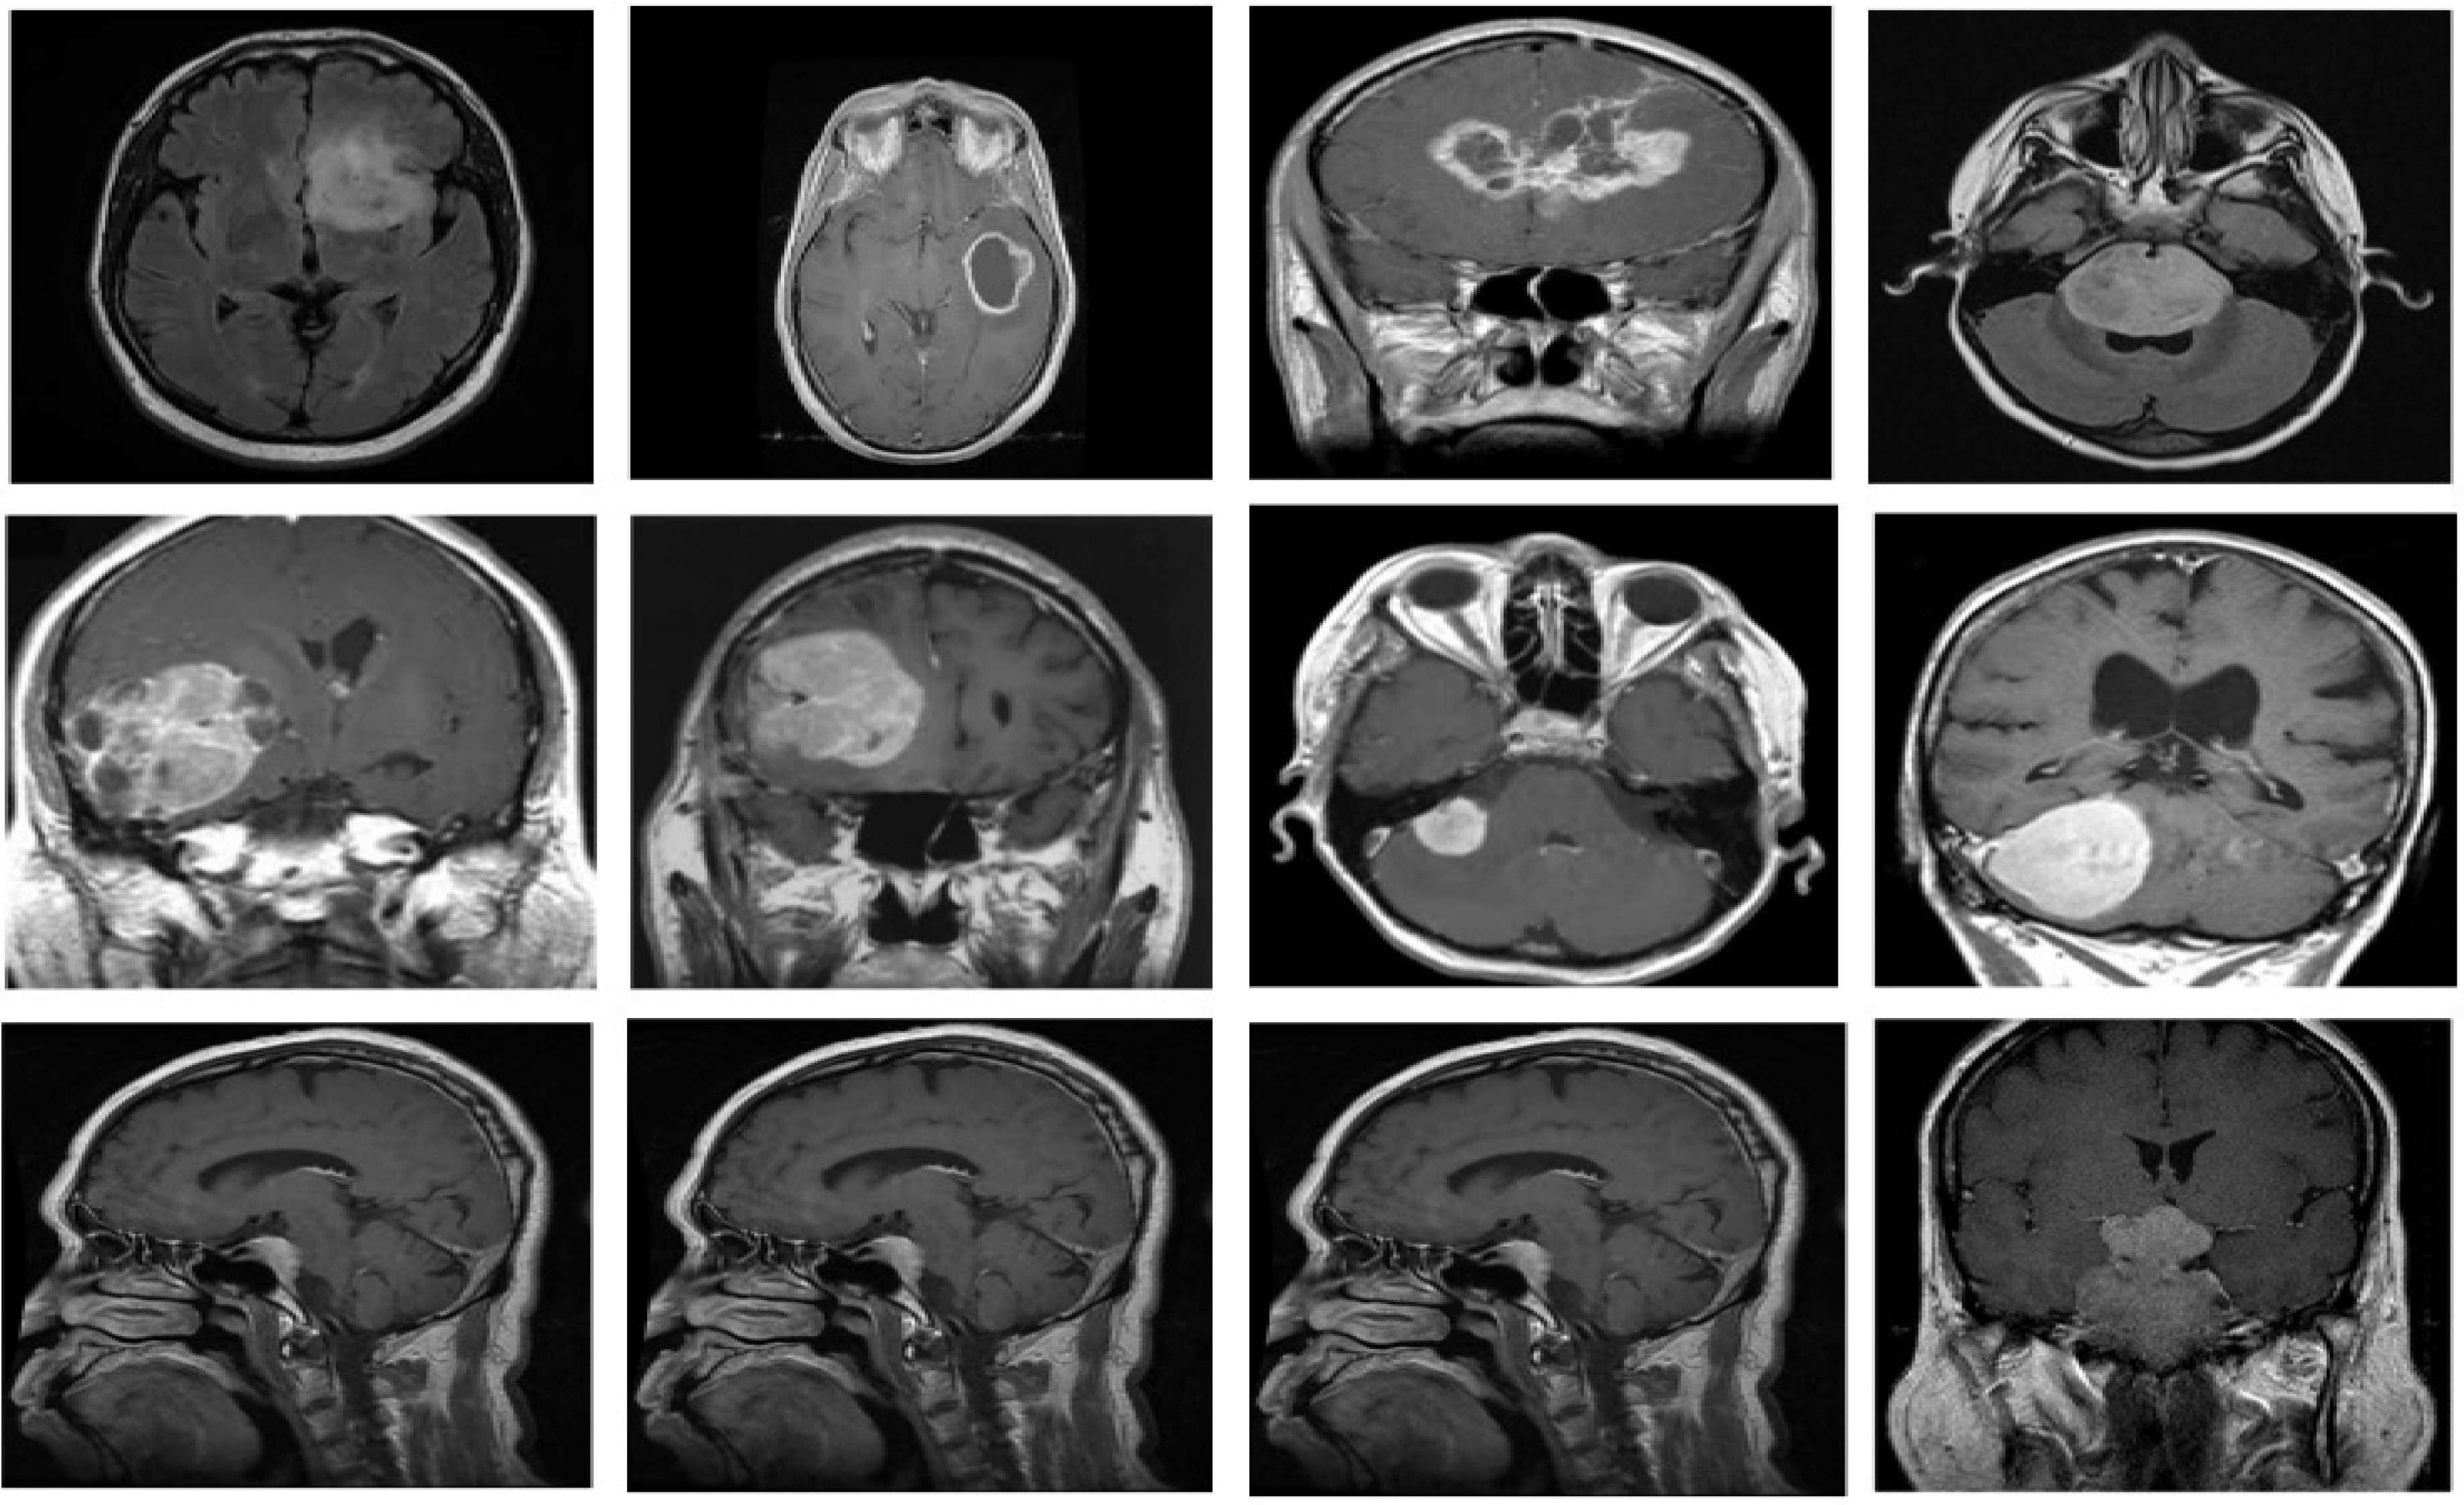

For the proposed fine-grained classification approach, we employed the brain tumor classification (MRI) dataset [35] to test, train and validate the different TL-based approaches, with the intention of identifying the best DL classifier. The dataset is freely available as a standard Kaggle dataset. The dataset comprises two brain tumor MRI image collections, i.e., testing and training. Each collection contains four types of brain tumor MRI images, i.e., no tumor, meningioma tumors, pituitary tumors and glioma tumors. However, we only used the meningioma, pituitary and glioma tumor MRI images. The latest version of the research dataset contains 822 MRI images of meningioma, 827 MRI images of pituitary tumors and 826 MRI images of glioma brain tumors in the training folder. The samples from each brain tumor category are shown in Figure 3. Moreover, the testing folder contains 115 images of meningioma, 72 images of pituitary tumors and 100 images of glioma brain tumors. We combined images from both folders. Then, 80% of the data was used for training, and the remaining 20% was used for testing. The dataset comprises grayscale images of different resolutions. In the preprocessing stage, the MRI images of the dataset were resized by using the augmented image data store according to the image input size requirements of different DL models; for example, for mobilenetv2, MRI images were resized to 224 × 224, and for darknet19, images were resized to 256 × 256. The details of the research dataset adopted for brain image classification are shown in Table 1, which describes the number of images against each tumor type, image format and brain image type.

Figure 3. Samples of the brain tumor classification (MRI) dataset, upper row: Glioma tumor, middle row: meningioma tumor, and lower row: pituitary tumor.